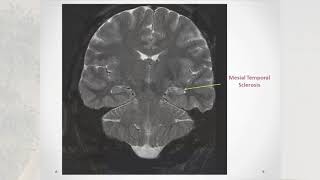

Natus EEG Webinar: Basics of Long-Term Video-EEG Monitoring: The Epilepsy Monitoring Unit (EMU)

Mark Quigg, M.D., M.Sc., F.A.N.A., F.A.E.S. Objectives: • Basic functions and protocols of an EMU • Epilepsy testing equipment and procedures • Epilepsy types ...

Natus Neuro